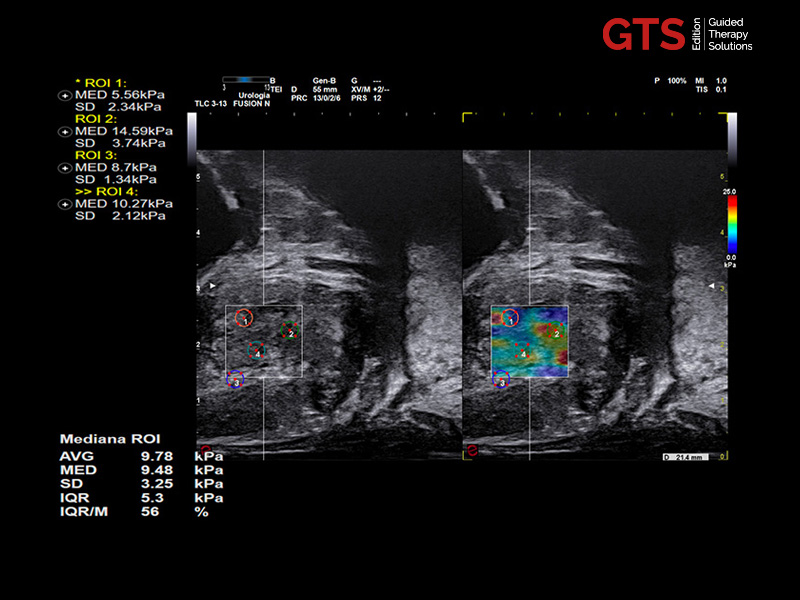

ElaXto and QElaXto 2D are Esaote’s strain and shear wave elastography technologies, which provide information on tissue elasticity by displaying a color-coded map representing prostate stiffness either relatively or quantitatively.

QElaXto 2D on sagittal view in suspected anterior region